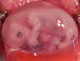

A

magzat az emlősállatok és az ember ivadéka a méhen belüli fejlődés szakaszában. Az embernél a 8. hétig (a test és a fő szervrendszerek kialakulásáig) embriónak, ezt követően a szülésig (a növekedés, érés időszakában) magzatnak nevezik.